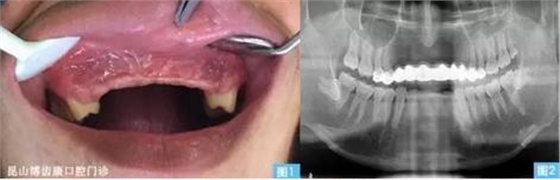

圖1圖2:患者主訴外傷后上前牙缺失約十年,要求種植修復(fù)。全景片發(fā)現(xiàn)缺牙區(qū)牙槽骨吸收嚴(yán)重,上唇部塌陷。